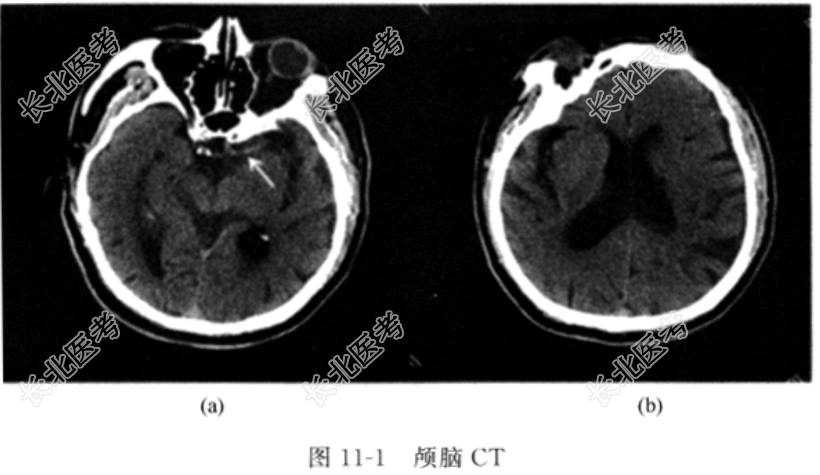

- [材料题] 患者,男性,78岁,主因“突发右侧肢体无力伴言语不能2h”于急诊就诊。患者2h前在家中活动时突然出现右侧肢体无力,完全不能活动,伴有言语不能,能听懂他人的言语,但自己表述不清楚,双眼向左侧凝视,无恶心、呕吐,无大小便失禁,无肢体抽搐,无全身出汗。自发病以来,未进饮食,未解大小便。既往史高血压30余年,血压最高180/90mmHg,规律口服缬沙坦控制血压,血压控制在140/80mmHg左右;糖尿病20余年,口服二甲双胍和阿卡波糖控制血糖,血糖控制良好;高脂血症10年,长期口服辛伐他汀治疗;冠心病5年,房颤3年,未特殊治疗。个人史吸烟40余年,约20支/天,已戒烟2年;否认饮酒史。护理检查体温36.5℃,呼吸18次/分,心率98次/分,血压150/90mmHg。心律绝对不齐,心音强弱不等,心率大于脉率。神志清楚,运动性失语,表情淡漠,双眼左向凝视,伸舌不配合。右侧肢体肌力0级,肌张力降低,左侧肢体肌力5级,肌张力降低,右侧病理征阳性。辅助检查颅脑CT检查示CT左侧大脑中动脉高密度征[图11-1(a)],CT未见明显低密度影[图11-1(b)]。

入院诊断急性脑梗死。主要的护理问题:(1)躯体活动障碍与脑组织受损、偏瘫有关。(2)语言沟通障碍与大脑语言中枢功能受损有关。(3)有皮肤受损的危险──压力性损伤与偏侧肢体瘫痪不能自主活动有关。(4)生活自理缺陷与肢体活动障碍有关。目前的治疗措施:尽快静脉溶栓联合脑血管介入治疗,该患者予以全脑血管造影+机械取栓术,术后予以抗血小板药物以及降压。